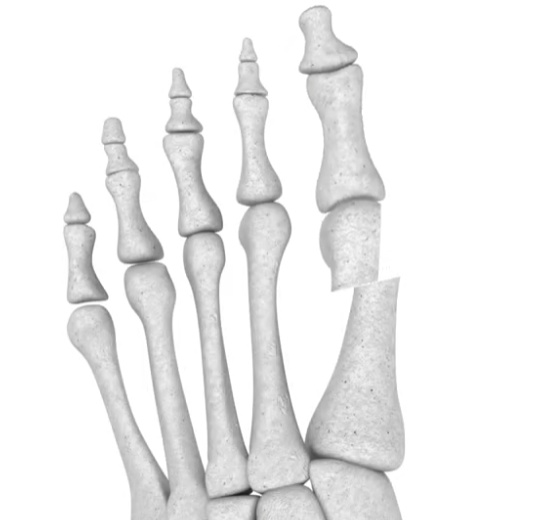

图注:Spear Plate 拇外翻矫形内固定器:专为亚洲人骨骼解剖曲线设计

·亚洲定制设计:基于亚洲民族骨骼数据库进行 3D 重建设计,更贴合亚洲人的骨骼解剖曲线 。

·髓内支撑:将钢板植入第一跖骨髓腔内,提供极强的生物力学稳定性 。

·精准矫形:提供 1mm、3mm、5mm 多种偏心距选择,实现“量体裁衣”式的精准矫正 。